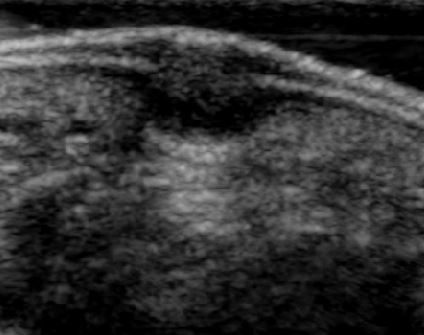

This destroys the tissue and causes a small blister to form over the spot. The following report covers our observation of 25 patients treated with ultrasound therapy. These ultrasonic findings are typical of a plantar wart and should not be confused with the inflammatory changes associated with a foreign body.

What is the best method in the use of ultrasound for treatment of plantar warts. Foot ultrasound of plantar fibromatosis plantar plate tear rupture mortons neuroma mulders click metatarsalgia effusion foreign body GooGhywoiu9839t543j0s7543uw1. Ultrasound can provide detailed anatomical data on warts and their inflammatory changes in the surrounding tissues. These ultrasonic findings are typical of a plantar wart and should not be confused with the inflammatory changes associated with a foreign body.